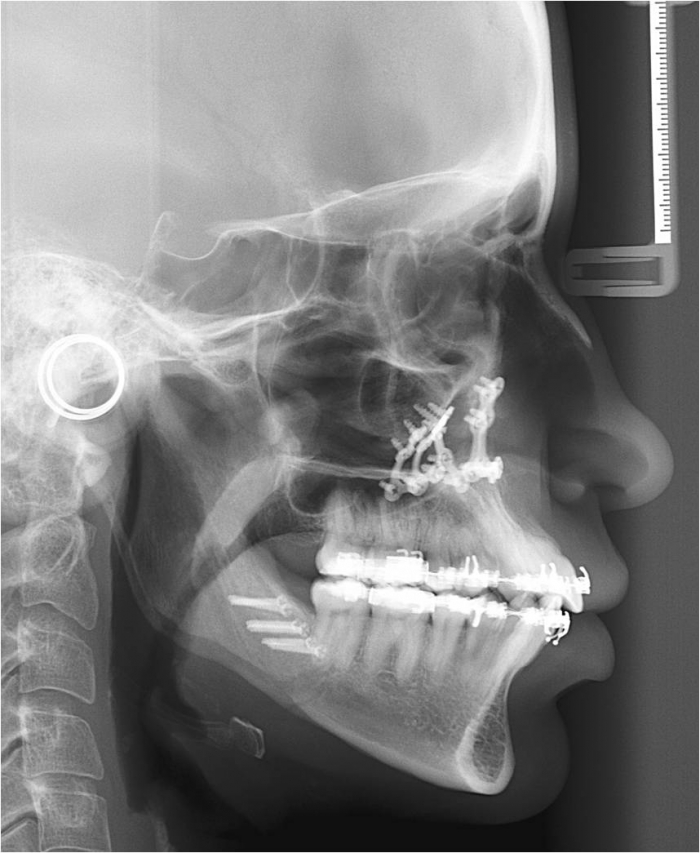

Telerradiografia inicial

Telerradiografia após a cirurgia